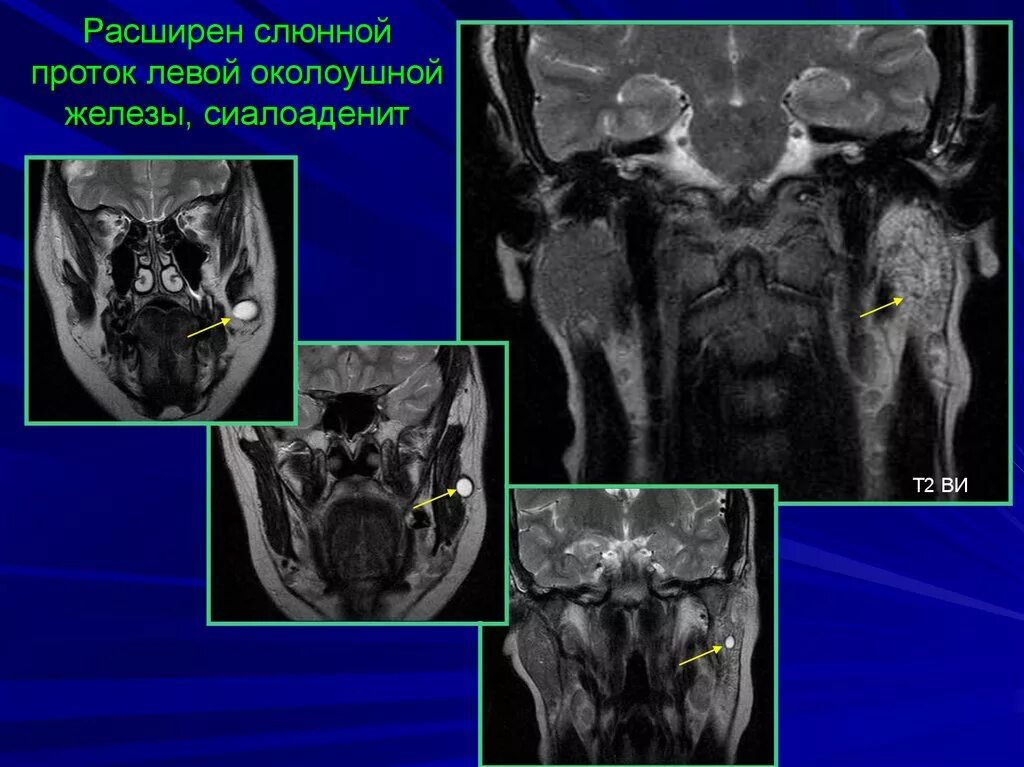

Расширен проток